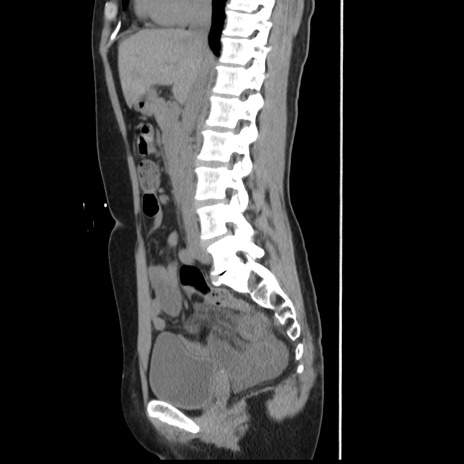

症例10(矢状断像)

【症例】 50歳代女性

【主訴】 腹痛

【現病歴】前日生レバーを食べた。今朝に排便あり。 昼前に突然発症の腹痛を生じ、当院救急外来を受診した。

【既往歴】 子宮筋腫にてで子宮全摘後

【身体所見】 意識清明、腹部:平坦、軟、下腹部やや左を中心に圧痛・反跳痛あり、筋性防御あり

【データ】WBC 7800、CRP 0.07